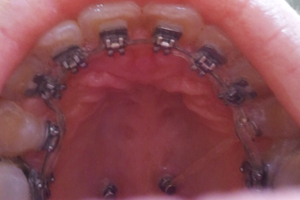

교정은 잘 되고 계신가요~?!!저는 이제 강남센트럴치과 15번째 월치료를 10월06일날 다녀왔습니당^^

이번 월치료에는 하악 철사를 바꾸고^^~ 상악은 잇몸때문에 못부쳤던 교정기를 부치고 철사를 다시 끼웠어요^^